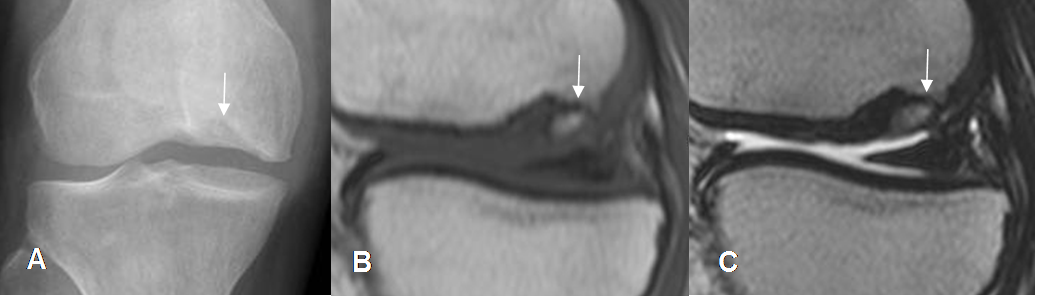

Fig 203. Lesión osteocondral inestable.

A: Rx AP. Area densa sobre el cóndilo femoral lateral.

B: RM sagital en T1. La imagen corresponde a lesión osteocondral.

C: RM coronal en STIR y D: RM coronal en T2. Lesión osteocondral con bordes hiperintensos, lo que indica inestabilidad.